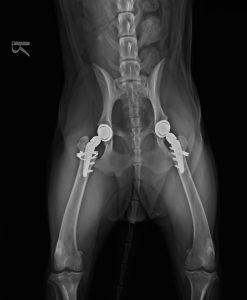

ケースレポート No.5 股関節全置換手術 バーニーズマウンテンドッグ(両側)

バーニーズ・マウンテン・ドッグ / 9ヶ月(初診時) / 体重 23.4kg

診断:両側 股関節形成不全

2023年2月 右 THR(股関節全置換術)実施

術後 1ヶ月のレントゲン画像

2023年5月 THR(股関節全置換術)実施

左 術後 1ヶ月のレントゲン画像